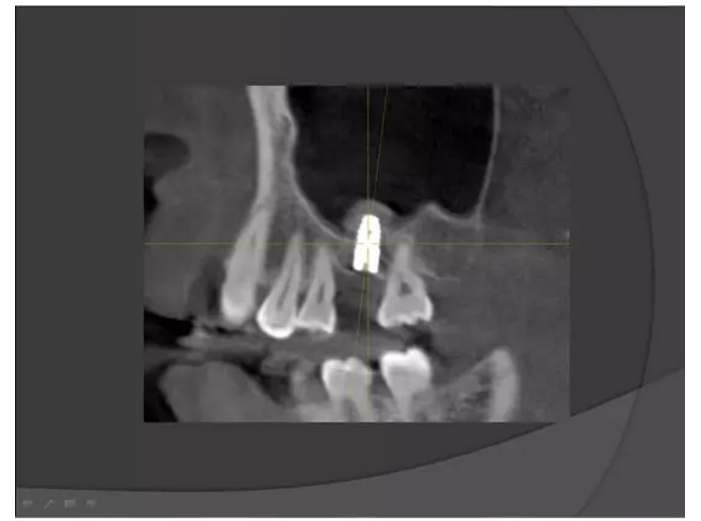

上頜竇種植手術(shù)概述

王漢禹